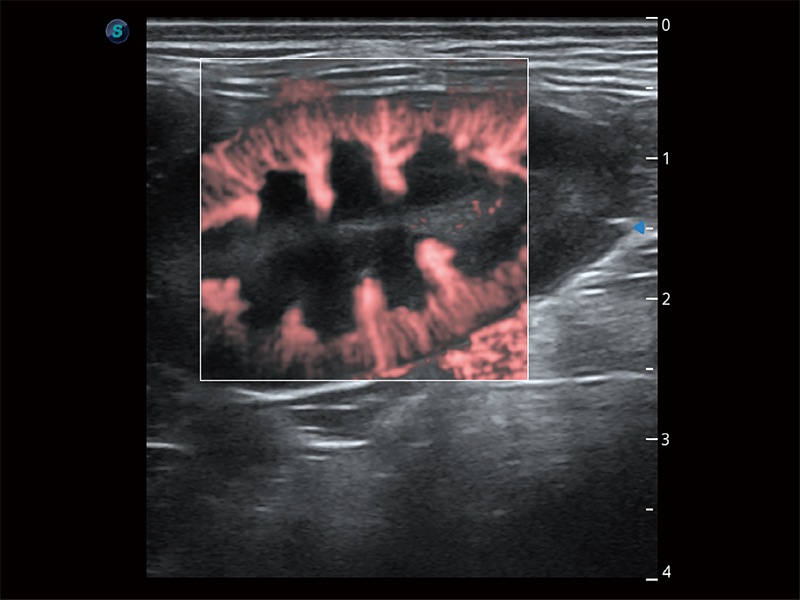

实时用颜色表示心肌组织运动,观察和定量组织的运动情況,对快速检测与评估心肌的灌注和活性、电传导及心肌收缩和舒张功能等均能提供重要的诊断信息。

通过心肌识别技术与二维斑点追踪技术相结合,对心脏的超声图像进行量化分析。计算心肌17个节段的应变、应变率、速度、位移等,并通过牛眼图的形式进行呈现。